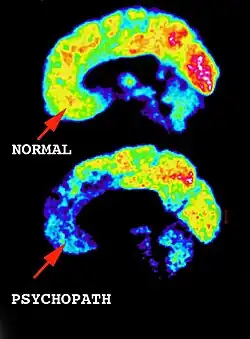

Brain activity comparing a healthy individual to a known psychopath. The psychopaths brain is lacking activity within the frontal lobe area, where emotions are processed.

Due to media and the entertainment industry, the terms psychopath and sociopath are the most common term associated with any serial killer. Psychopath is the term used to define someone who is suffering from a prolonged mental illness with symptoms including violent and abnormal social behaviour, like having no emotions (Blair, Mitchell, & Blair, 2005). Being a psychopath isn’t itself a motivator for serial killing but is factored into the motivation due to the individuals lack of control and their violence. A sociopath is similar to a psychopath, where the individual is suffering from mental illness but symptoms include extreme antisocial attitudes and behaviours, like lacking a moral code, and not understand local culture (Thomas, 2013). These two types of disorders can make an individual lose control and in some rare instances make one kill, or have a compulsion to kill (Edens et.al., 2013). The lack of control and the lack of either social behaviour or violent tendencies can motivate an individual to do unstable-like activities, like having a compulsion to kill.